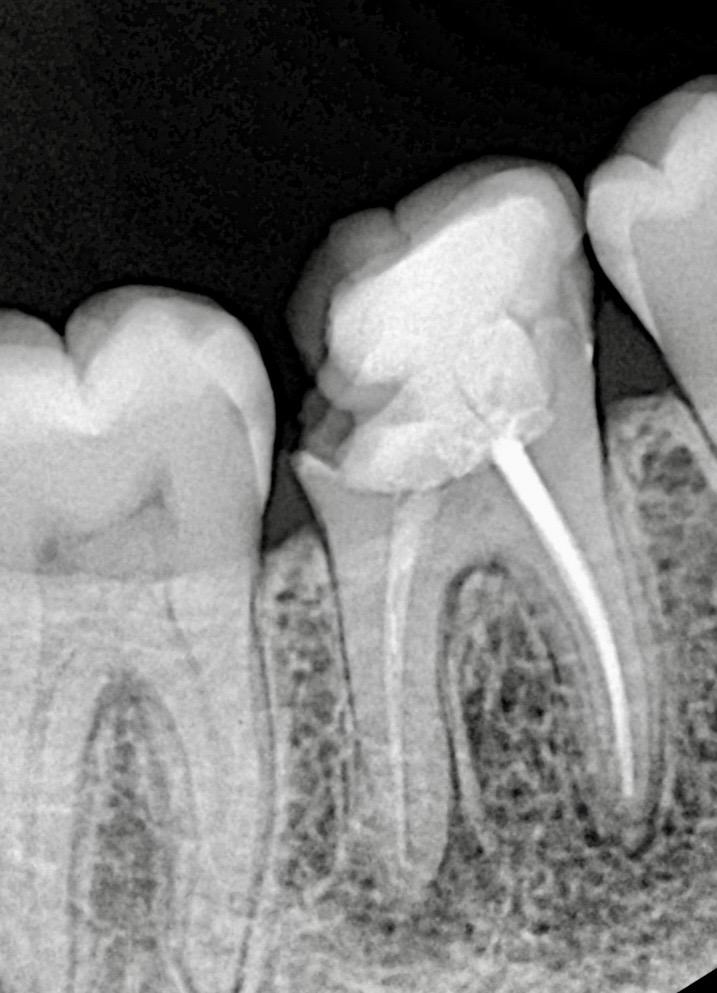

- Working length established using electronic apex locator.

- Full irrigation protocol activated using:

- 5.25% NaOCl (heated)

- 17% EDTA

- Ultrasonic activation

- Apical patency regained and canal shaping completed using reciprocating NiTi files.

- Canals obturated using warm vertical compaction and bioceramic sealer to optimise apical seal.